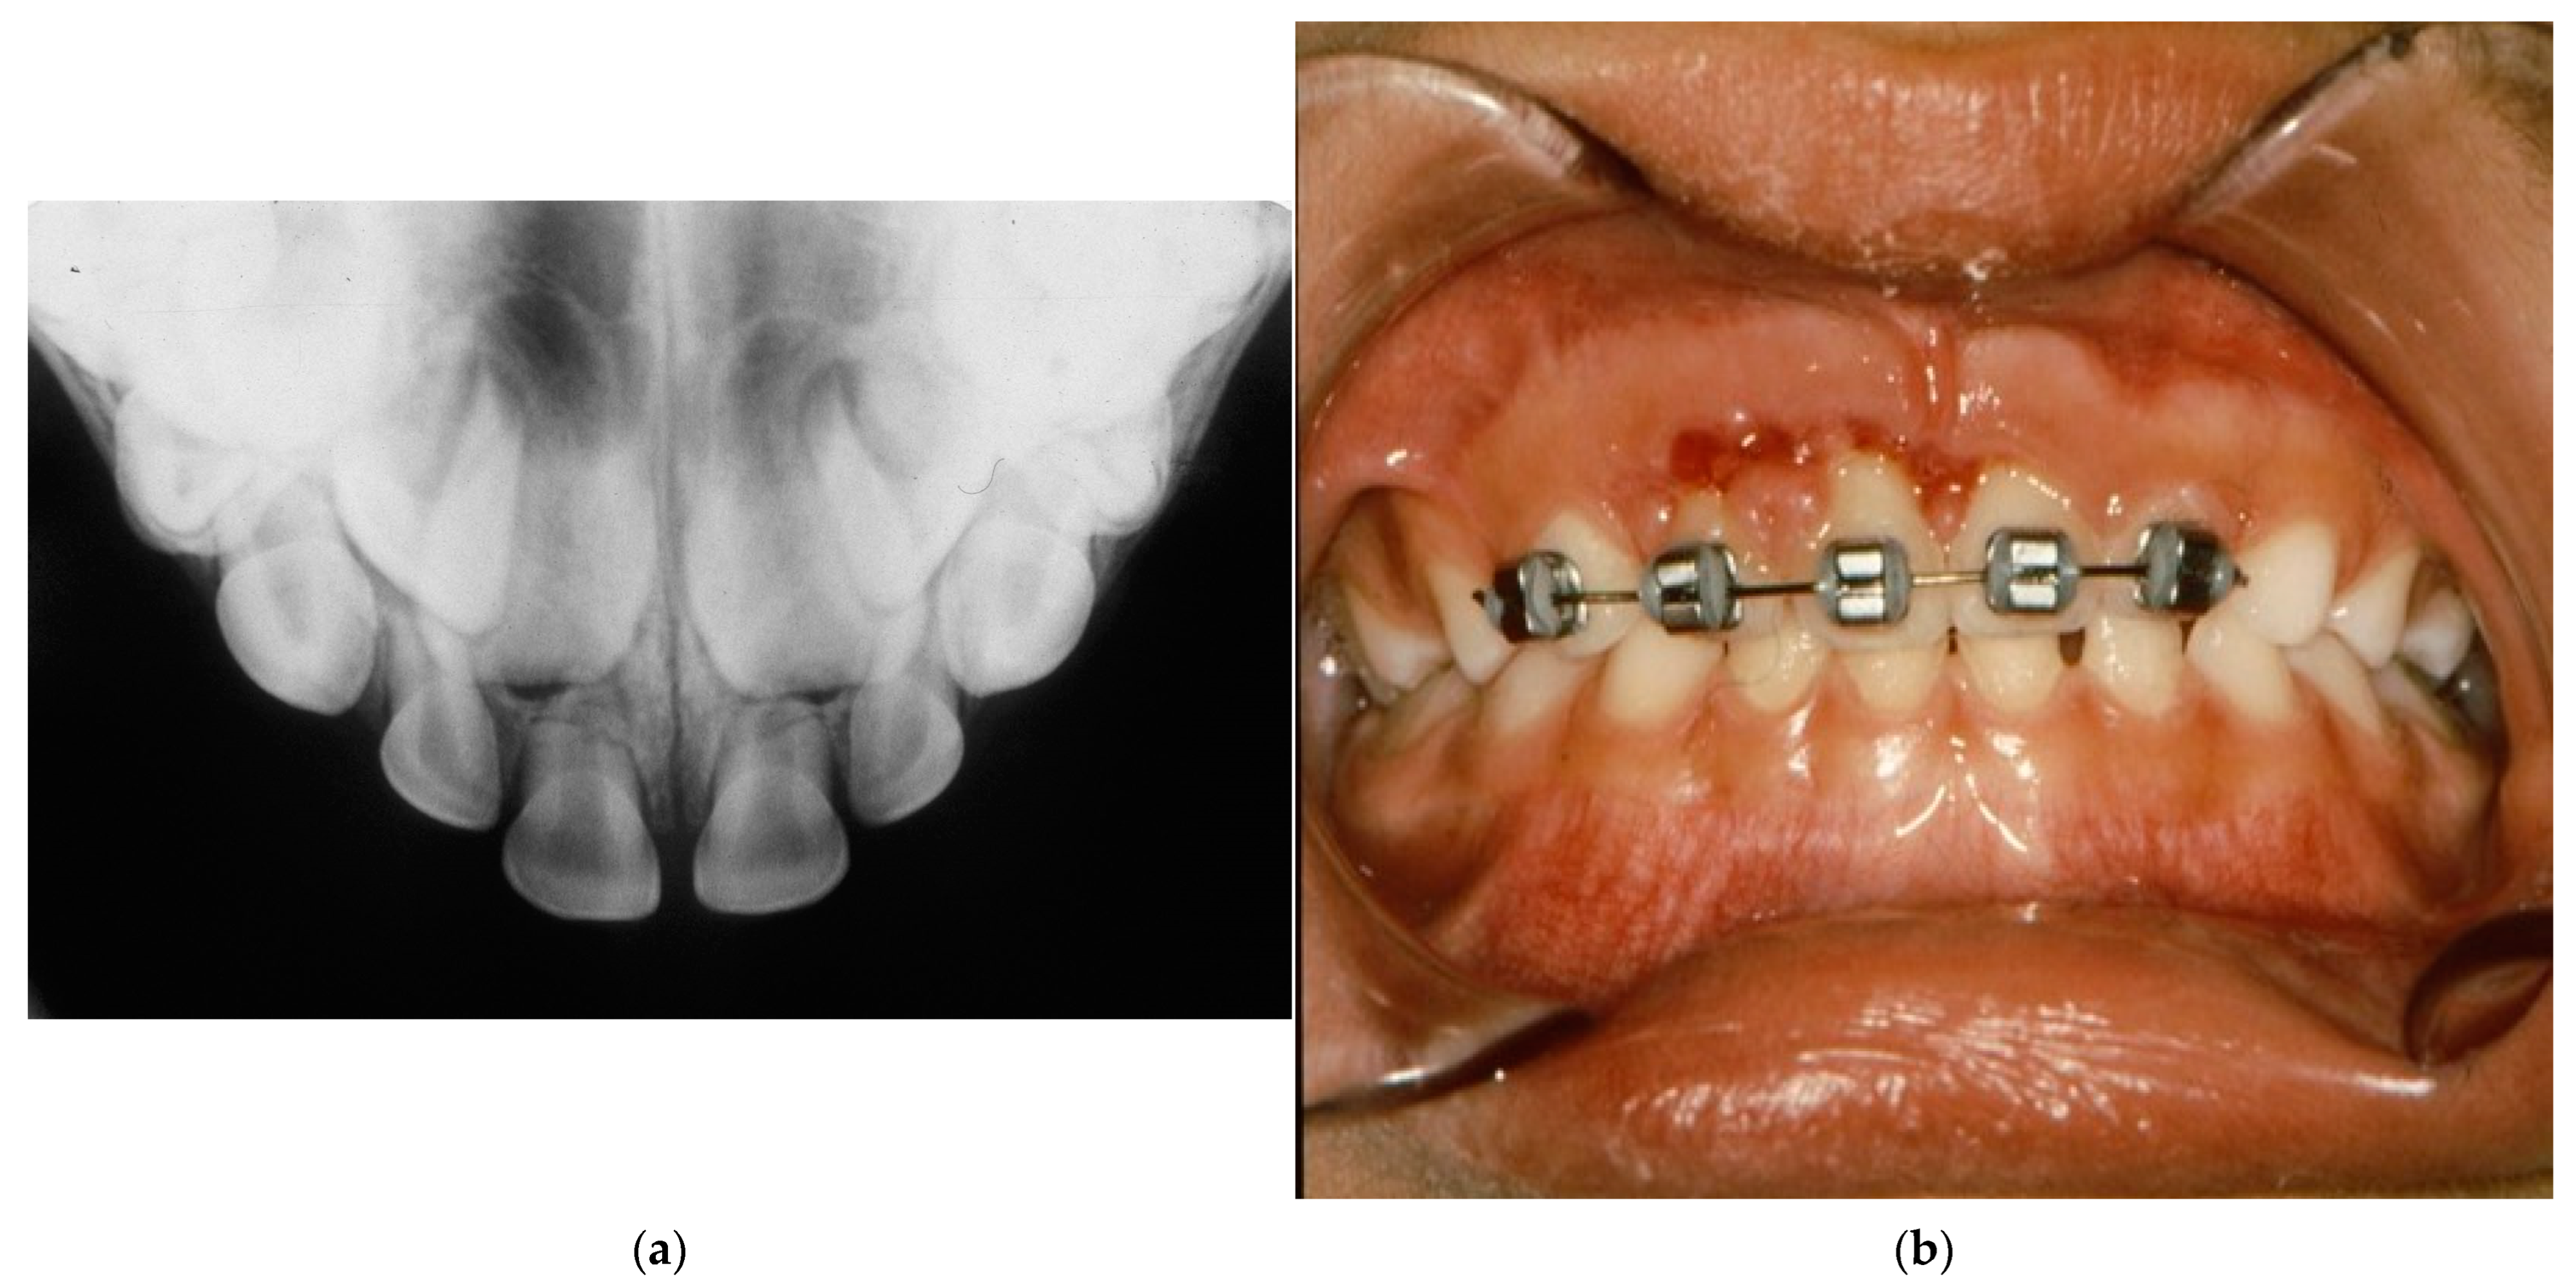

- Non-rigid/semi-rigid/flexible splinting: allows for physiological functional mobility of the traumatized tooth, promoting healing of the periodontal ligament with a consequent reduction of the risk of ankylosis.

- Conditioning of the enamel of damaged and nearby teeth;

- Application of adhesive and composite material to the affected tooth and adjacent teeth;

- Light curing to harden the composite material.